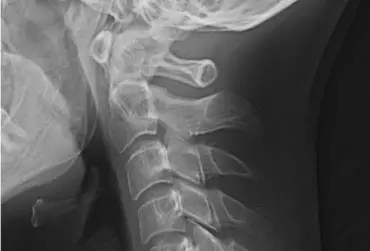

Szyja smartfonowa – diagnostyka oraz leczenie – wyzwanie XXI w.

Zespoły bólowe w zakresie narządu ruchu są coraz częściej obserwowane w społeczeństwie, nie tylko w grupie pacjentów starszych, ale również u młodzieży i młodych dorosłych. Poza typowymi dolegliwościami, jakimi są ból oraz ograniczenie ruchomości w zakresie objętego patologią narządu, pojawiają się inne symptomy chorobowe, które utrudniają codzienne funkcjonowanie, są trudniejsze do kontrolowania oraz leczenia. Należą do nich m.in. nudności, zawroty głowy, zaburzenia: widzenia, słuchu oraz równowagi. Objawy te mogą występować w przebiegu zespołu szyjno-głowowego, tzw. szyi smartfonowej.

Protokół postępowania w przypadku dolegliwości bólowych kręgosłupa szyjnego wywołanych przepukliną z wykorzystaniem terapii ENF

Przepuklina kręgosłupa to poważny stan, który wiąże się z ostrymi lub przewlekłymi dolegliwościami bólowymi. Może prowadzić do ograniczenia ruchomości oraz problemów neurologicznych. Fizjoterapia pacjentów z przepukliną powinna być przeprowadzona w sposób ostrożny i dokładny, aby nie wywołać niepożądanych skutków terapii.